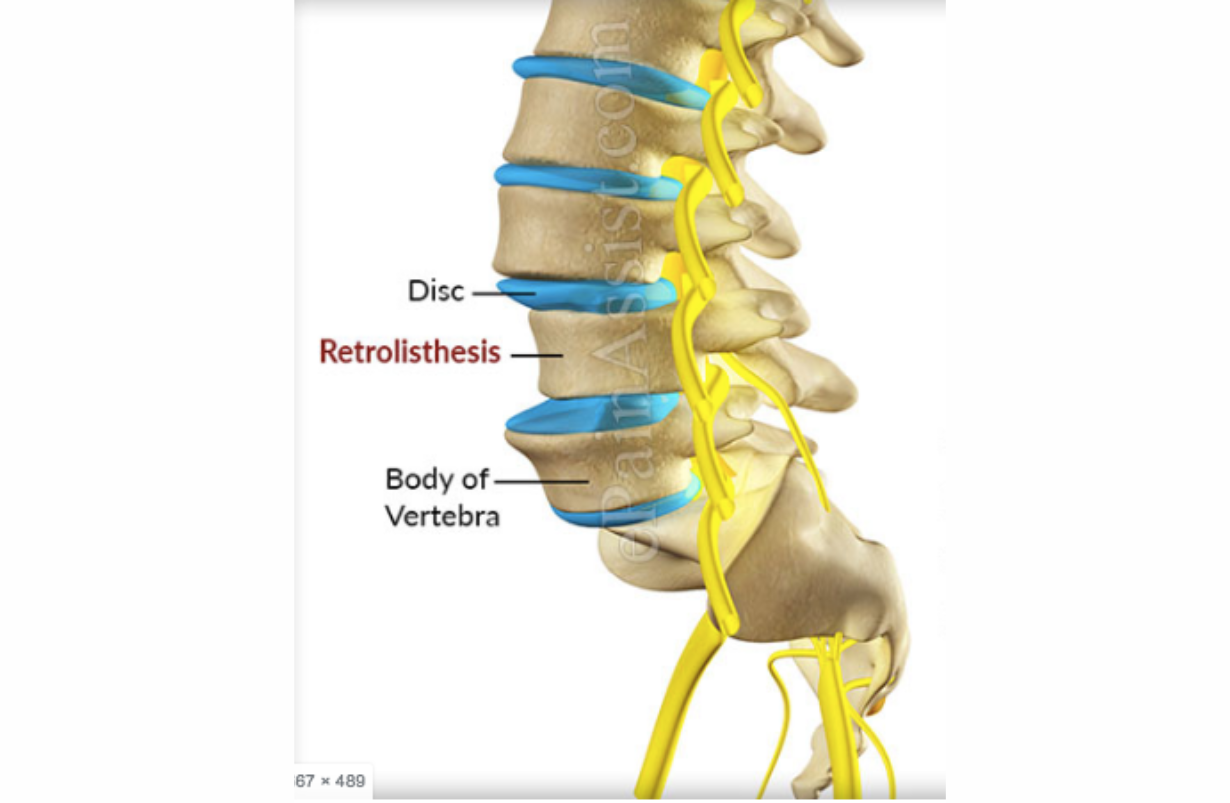

Retrolisthesis

DEFINITION: Backward sliding of one vertebra relative to the one below it: Grade I - 1-25% Grade II - 25 - 50% Grade III - 50 - 75% Grade IV - 75 -100% BENEFICIAL POSES: Salabhasana, Dhanurasana, Eka Pada Viparita Dandasana, Paripurna Navasana, Ardha Navasana, Parsvottanasana. EXPLANATION: Contraction of back muscles has two effects: arching the back, which 1. Exerts gentle forward pressure on the vertebra that has slid backward , and 2. opens the front of the vertebrae, giving room for the backward placed vertebra to slide forward.. Doing these extension poses facing downward further engages gravitational forces to move the errant vertebra forward and back in line with those above and below it. After these three intensely extending poses, it is wise to conclude with Dandasana, Paripurna Navasana, Parsvottanasana. REFERENCE: The authors found no studies of yoga for retrolisthesis, or spondylolisthesis in general, but these poses are recommended by Loren Fishman, MD on the basis of decades of clinical experience.

Spondylolisthesis

Spondylolisthesis occurs when one vertebra slides forward, backward or to the side, relative to the one directly below it. This slippage can occur in the cervical, thoracic (much less commonly) or the lumbar spine, and is generally forward slippage, anterolisthesis. Retrolisthesis is backward slippage of the vertebra above, and lateral listhesis involves slippage to one side or the other. Regardless of the direction, spondylolisthesis is graded in one way: Grade I: 0 - 24.9% of the lower vertebra is uncovered, Grade II: 25 - 49.9%, Grade III 50 -74.9%, and Grade IV: 75% or more. Anterolisthesis and retrolisthesis can cause all the neurological symptoms of a herniated disc or spinal stenosis, because it can narrow the spinal canal nd also shrink the opening through which the nerve root leaves the spinal cord (neuroforamen). .Generally Grade I is painless, though there are exceptions when e.g., the facet joints are swollen from arthritis, or there is a bulging or herniated disc narrowing the opening in the spine through which nerve roots exits (neuroforamina). However even Grade I, and certainly higher grades can leave the intervertebral disc uncovered by the vertebra above, and this can lead to paraesthesias, numbness, pain and weakness, and even bowel or bladder symptoms in extreme cases. Most cases are traumatic in origin, but some authorities assert that it can be congenital, particularly when the bone connecting the facets to the vertebral body (the pars interarticularis) is fractured. Yoga is particularly useful in the most common type of spondylolisthesis, anterolistghesis. In general with anterolisthesis, the strategy is to move back the forward-slid vertebra. Abdominal strengthening and forward bending, making the spine as long as possible, are the poses that do this. Retrolisthesis is treated just the opposite way: strengthening the quadratus lumborum muscles, and doing back extension poses. Lateral listhesis is rarely symptomatic, although it makes the yogic treatment of scoliosis more difficult. See 'scoliosis' for details.